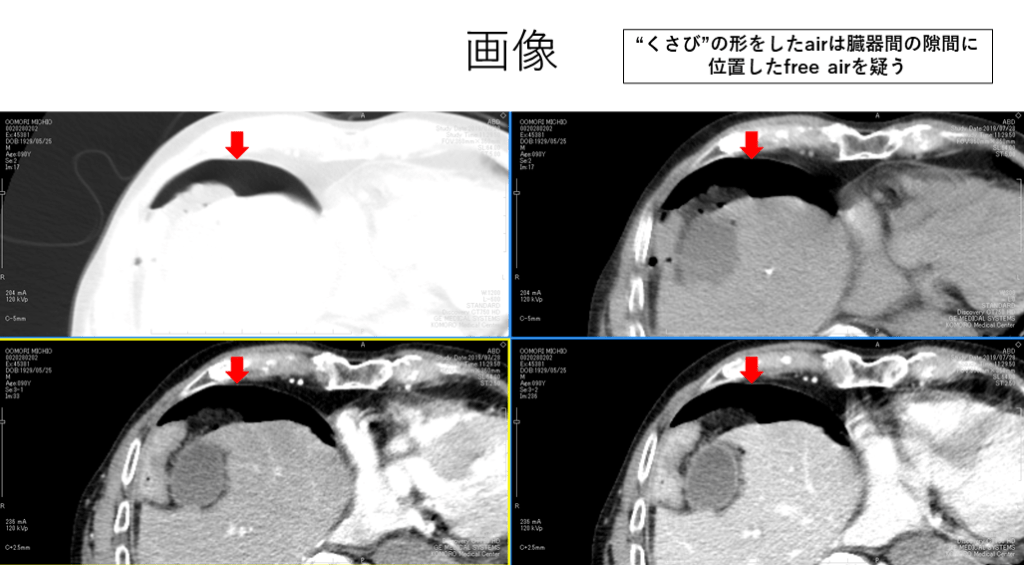

画像 “くさび”の形をしたairは臓器間の隙間に 位置したfree airを疑う

Take home message ・free airを検索する際には肺野条件と他条件を並行して検索が有用。 ・腹部条件だけだとairを見落とす可能性がある。 ・free airと見分けにくい構造に注意する。他条件との比較が重要。  (例:肺実質、腸管内ガス、濃度の低い脂肪織) ・腸管“内”or“外”を見分けるには根気強く腸管を追うしかない。